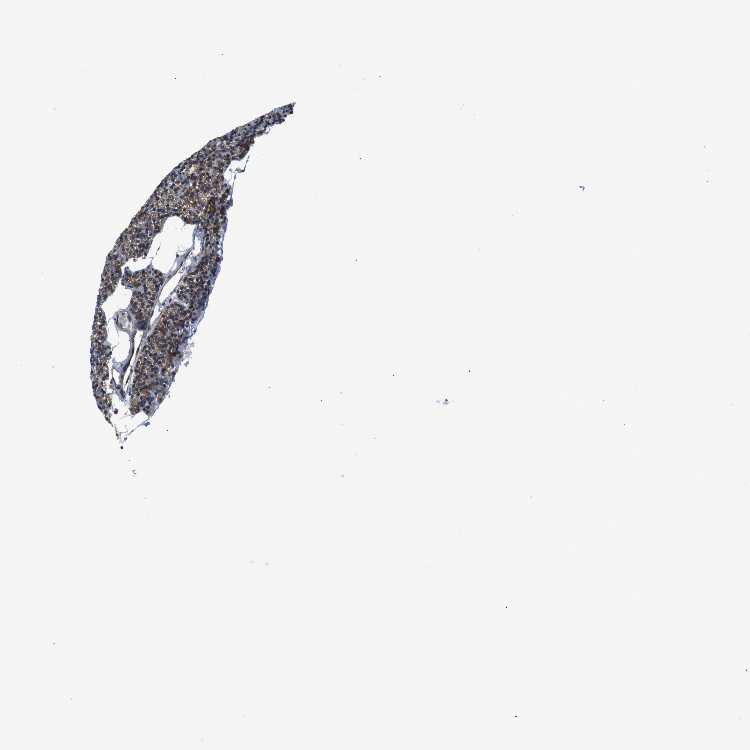

PARATHYROID GLAND - Antibody stainingi

Antibody staining in the annotated cell types in the current human tissue is reported as not detected, low, medium, or high, based on conventional immunohistochemistry profiling in selected tissues. This score is based on the combination of the staining intensity and fraction of stained cells.

Each image is clickable and will lead to virtual microscopy that enables deeper exploration of all samples and also displays staining intensity scores, fraction scores and subcellular localization as well as patient and tissue information for each sample.

Antibody HPA014837

Glandular cells Medium